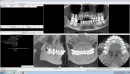

Прилагаю фото с КТ.

К сожалению, на представленных снимках нет изображения поперечного сечения (в области отсутствующего зуба). Без него невозможно сказать какова ширина альвеолярного гребня и рассчитать размер импланта. Но, если врачи говорили, что объем кости не позволяет, у меня нет оснований им не доверять. Область, действительно, с выходом нерва, и при подсадке кости возможно травмирование, что категорически недопустимо.